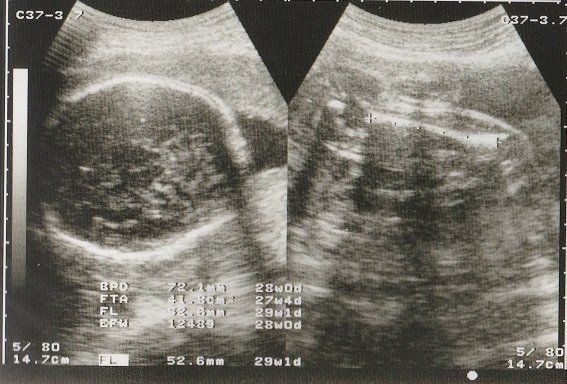

妊娠29週目のエコー写真 お母さんの体にむくみなどが出てくる時期

赤ちゃんの眼球が写っています。このころ、おなかのなかで赤ちゃんも寝たり起きたりしているそうです。

この時期になると、手足のむくみが気になるようになりました。